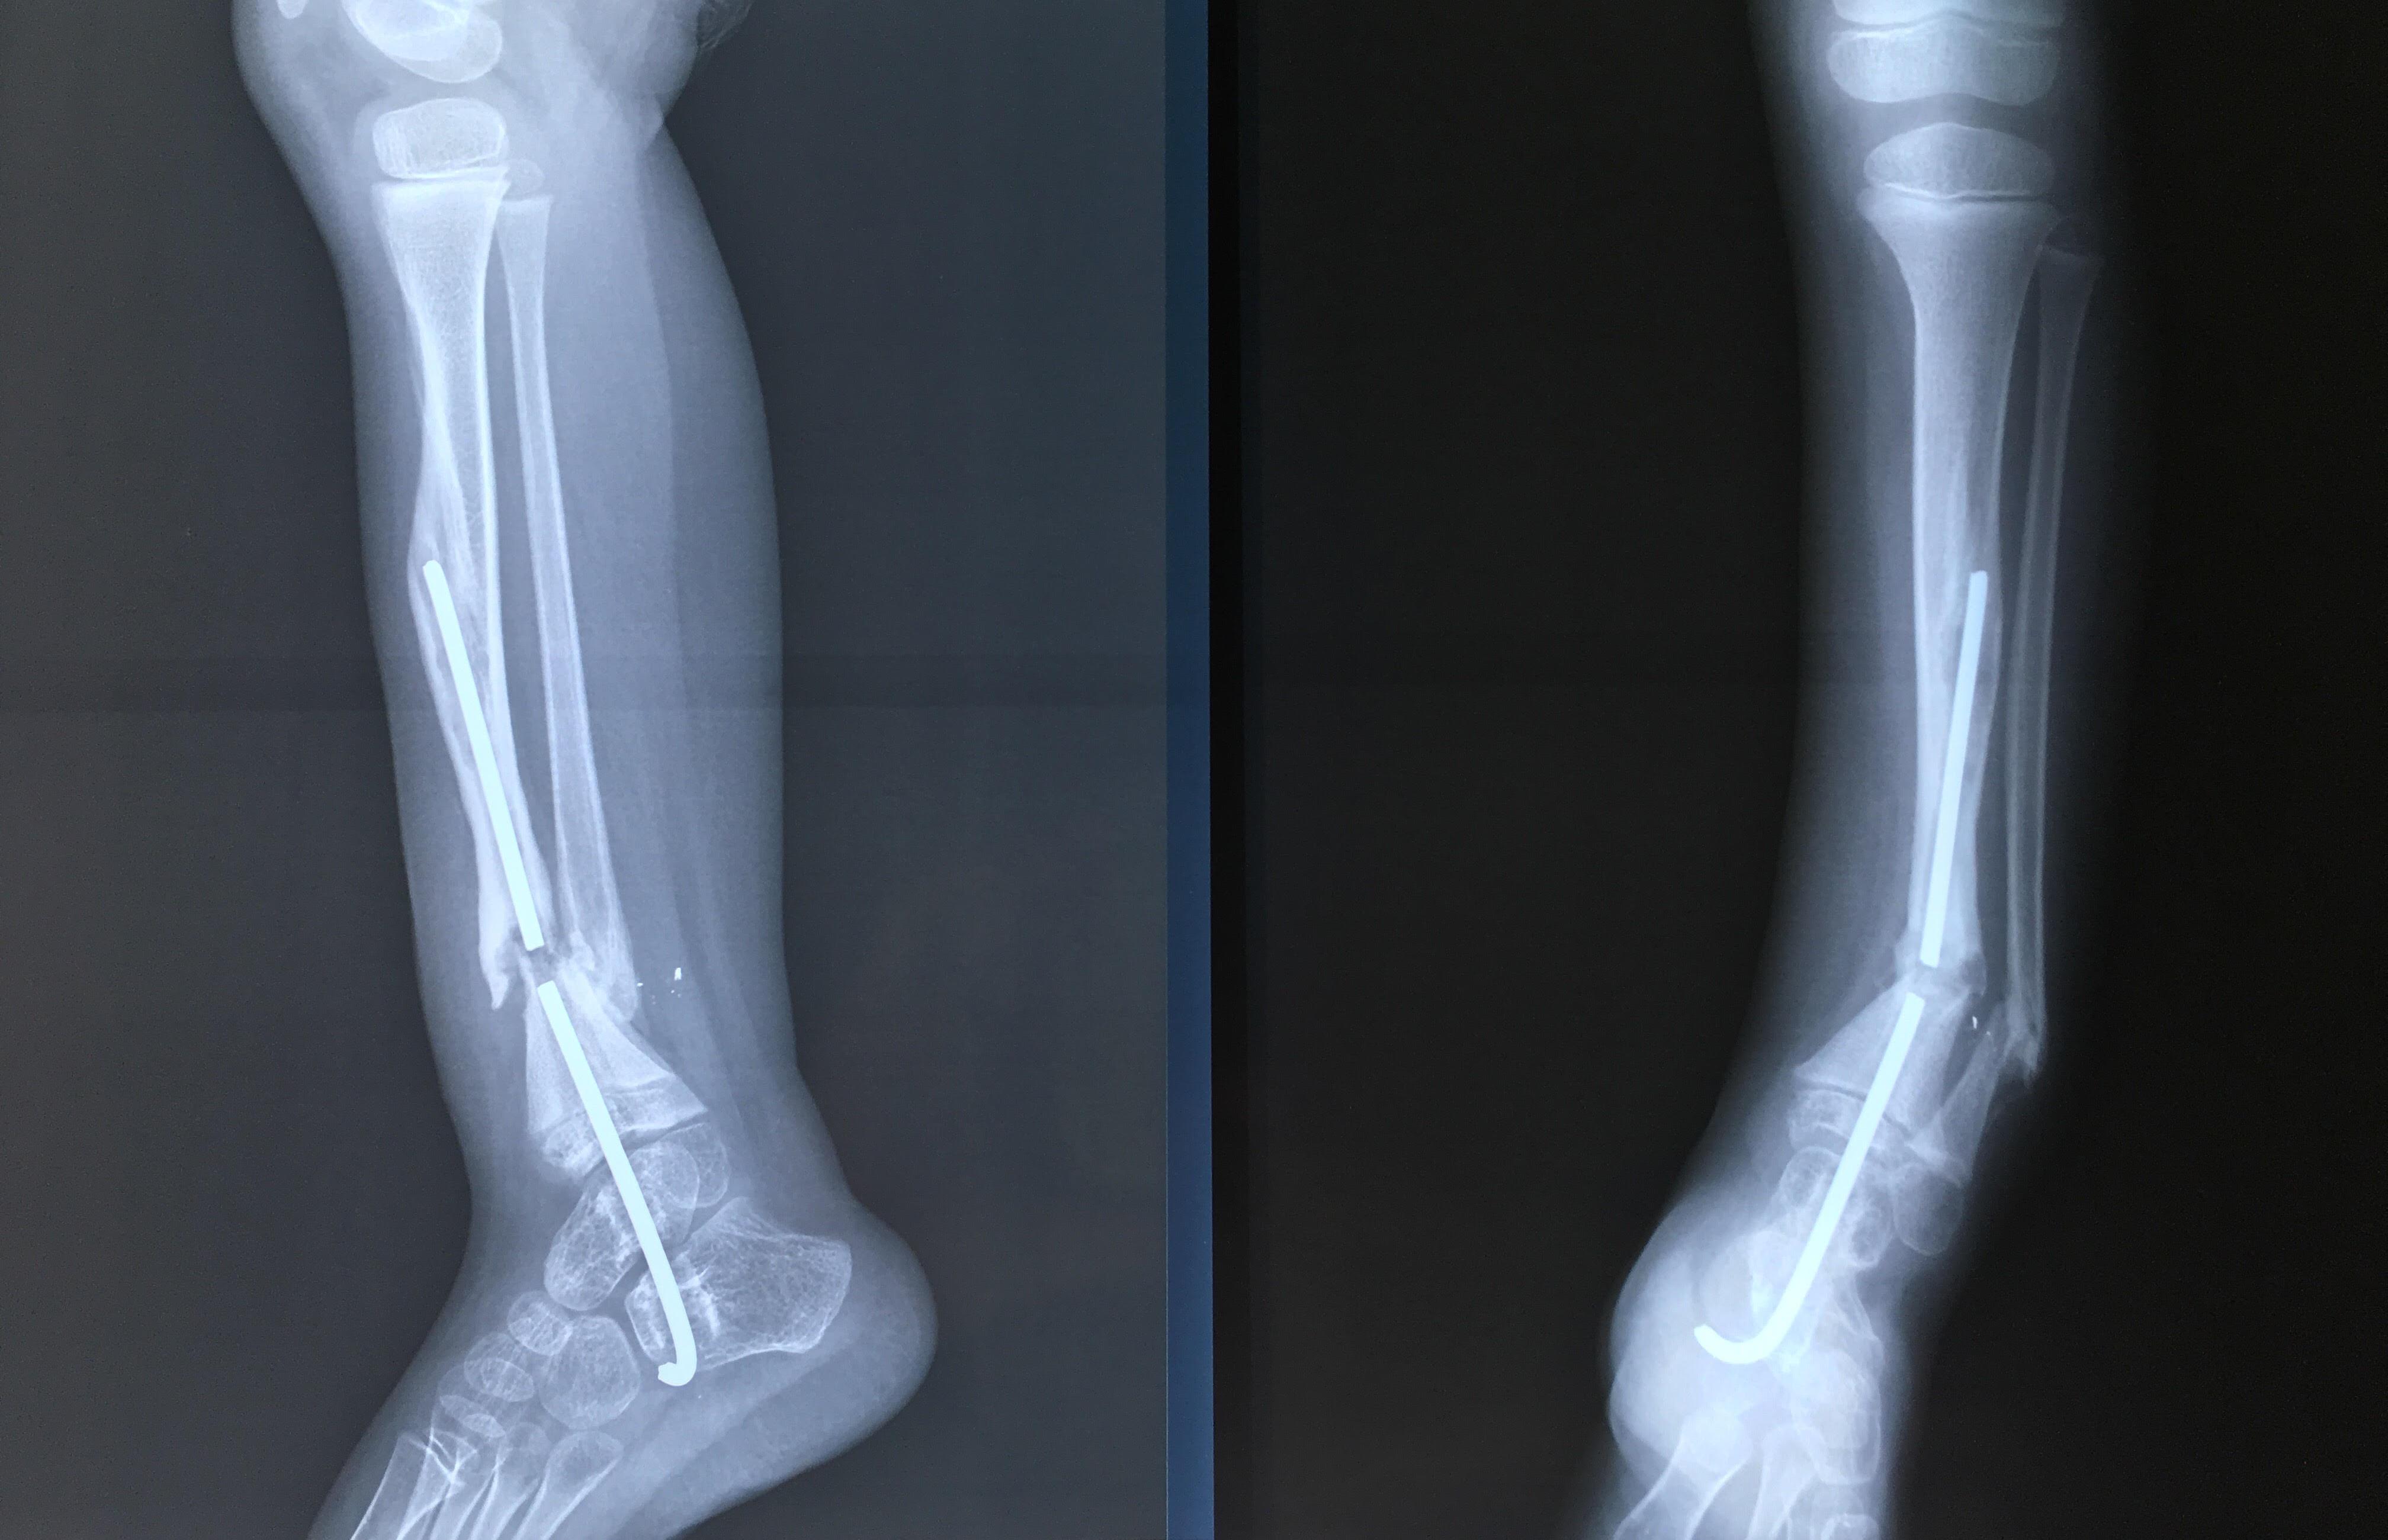

Phẫu thuật thành công ca bệnh hiếm gặp...khớp giả bẩm sinh xương chày

26/06/2019 17:00

Đã xem: 3474

Bệnh viện Chấn thương- Chỉnh hình Nghệ An, vừa phẫu thuật thành công cho bệnh nhi khớp giả bẩm sinh xương chày